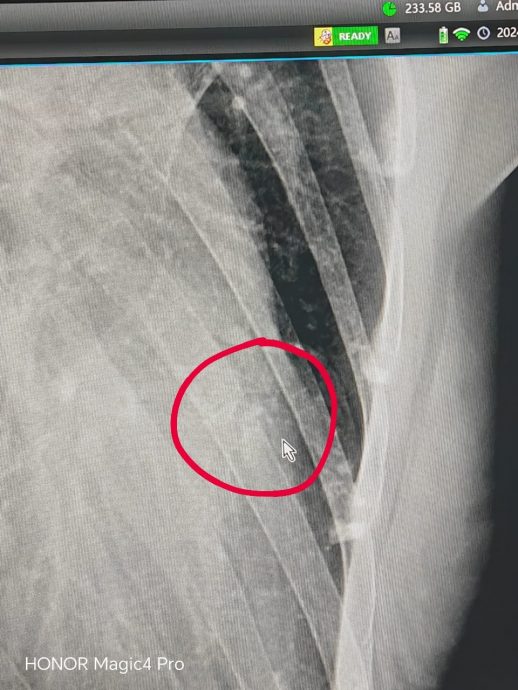

她说,她因被人勒颈差点断气而被送入急诊室;之后疼痛再次发作,第二次送入急诊室,脚肿无法走路,手脚有瘀青,经过照X光诊断左边肋骨第六根骨断裂。